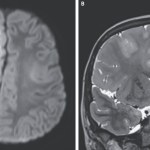

Tak wygląda mózg zniszczony przez odrę. A wystarczyło szczepienie

Przez lata odra była w USA chorobą praktycznie zapomnianą, bo po wprowadzeniu powszechnych szczepień w 2000 roku praktycznie ją wyeliminowano. W konsekwencji nasilania się nastrojów...odra -